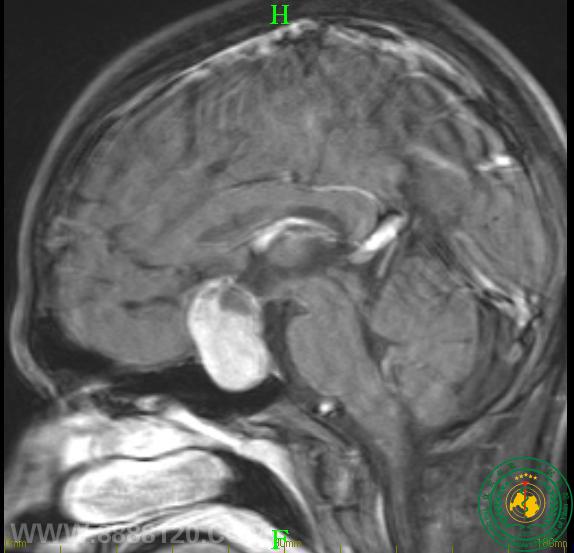

术前核磁共振图像及视野情况:

该患者经完善术前准备,由我科周世军副主任医师主刀,采用目前我市最新技术-神经内镜技术为患者切除垂体瘤,术后第二天,患者视力明显恢复,术后复查头颅核磁共振提示肿瘤全部切除。

术后复查核磁共振提示肿瘤全部切除。